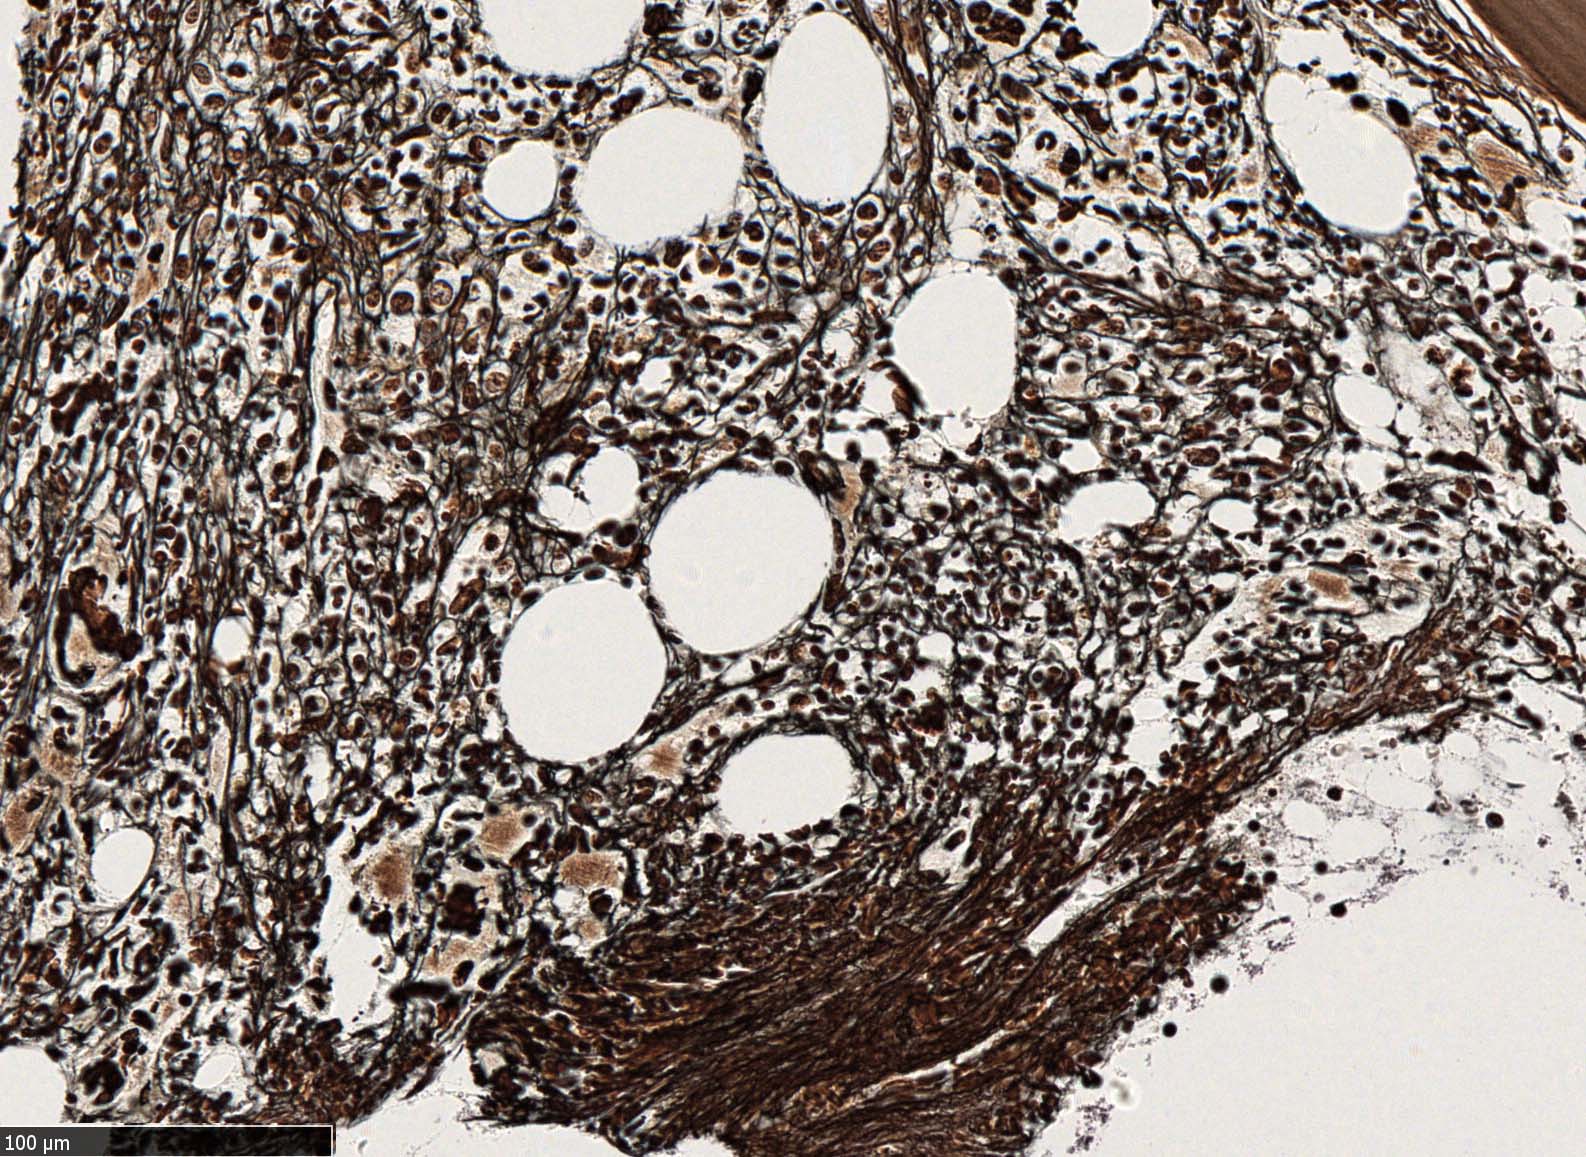

塗銀染色

黒染する弾性線維の増生のほか, 赤く染まる膠原線維の増生が確認される. MF-2 fibrosis. 鍍銀染色の核染色をすると膠原線維の赤染がわからなくなるので行わない.